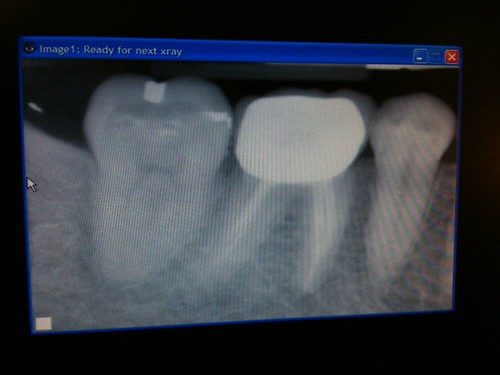

你帶小朋友到診所後,醫生首先會和小朋友進行簡單的互動,緩解其緊張情緒,隨後進行口腔全面檢查,並拍攝根尖X光片,清晰查看牙根的形態、長度、炎症範圍,以及下方恆齒牙胚的發育狀況。

治療完成後,醫生會再次拍攝X光片,確認根管充填的效果,隨後和你講解詳細的術後護理注意事項。通常會安排術後1周、3個月、6個月的複查,檢查牙齒的恢復狀況、炎症是否消退,以及乳齒下方恆齒的發育情況,確保治療效果長期穩定。